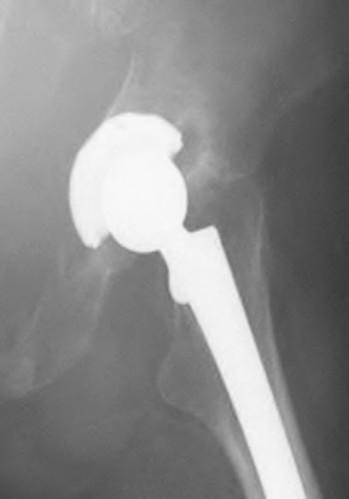

A 57-year-old man undergoes total hip arthroplasty, has an uncomplicated early postoperative course, and a normal neurovascular status is documented. However, on postoperative day two he develops a progressive foot drop that increases over the next 24 hours. Postoperative repeat radiographs of the hip arthroplasty are unrevealing. There is no suggestion of swelling of the thigh to suggest a subfascial wound hematoma. What is the next most appropriate step?